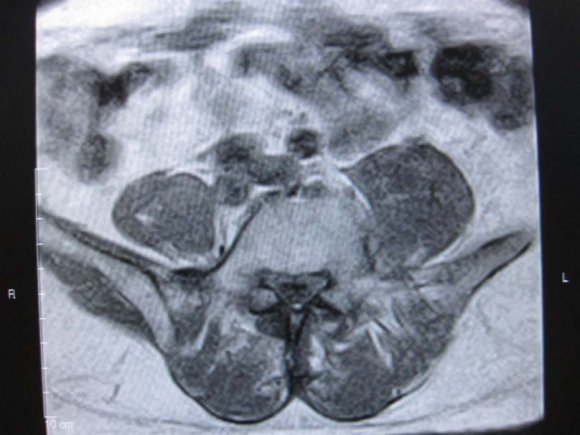

(b) there was no contraindications to MR imaging (e.g. pacemaker, aneurysmal clips, foreign body in globe etc). b) MRI Protocol MR imaging was performed at our hospital, using 0.3 Tesla Hitachi AIRIS 11 MRI machine, and spine phased-array coil. Technical factors used were T1W, T2W, STIR. Sagital acquisitions were used in screening while axial and coronal were used to evaluate the neural foramina. This was followed by T2 STIR images acquired in oblique coronal and sagital planes .Enhanced T1W images with Gadolinium pentate dimeglumine were used in cases of intra-spinal mass lesion or to evaluate herniated disc lesions where T2W images were degraded.

Technical specifications included a slice thickness of 3 and 4 mm for sagittal and axial sequences, respectively; a field of view of 26 and 20 cm for the sagittal and axial images, respectively; and a matrix of 192 by 256. The T 1 -and T 2 weighted axial sequences were stacked slices extending from the inferior aspect of L3 through the inferior aspect of S1.

Disc herniation can be used to describe a wide spectrum of abnormalities involving disk extension beyond the interspace, from a bulge to a frank extrusion and sequestration; [11]. The terms used to classify disks were defined as follows: normal, no disk extension beyond the interspace; bulge, circumferential symmetric extension of the disk beyond the interspace (around the end plates); protrusion, focal or asymmetric extension of the disk beyond the interspace, with the base against the disk of origin broader than any other dimension of the protrusion; and extrusion, more extreme extension of the disk beyond the interspace, with the base against the disk of origin narrower than the diameter of the extruding material itself or with no connection between the material and the disk of origin [9,11].Sequestered disc are free disc fragment which may migrate below or above the interspace [6]. On MRI examination of the lumbar spine, many people without LBP have disk bulges or protrusions but not extrusions, thus discovery by MRI of bulges or protrusions in people with LBP may frequently be coincidental [11]. There is a hypothesis that the prevalence of extrusions in people with symptoms of LBP may be substantially higher than in people without symptoms [11]. Sequestered or free fragment has high T2 * W signal because their increased water content produces an increase in signal intensity [6]. When it is behind the parent disc, it is round in configuration but oblong on further separation [6]. Annular defects or fissure which can be demonstrated by MRI as decreased signal on the T 2 -weighted image may be a fore-runner to disc hernia and are frequently asymptomatic [11] But any pain , possibly results from leakage of the contents of the nucleus pulposus into the epidural space, with related nerve irritation [11]. The reported prevalence of posterior radial tears at autopsy in asymptomatic people is 40 percent for those between In our study, no distinction was made between disc protusion and extrusion, rather cases where there is protusion of disc anteriorly and behind anterior longitudinal ligament was considered separately and termed disc anteropulsion. 6 cases (12.5%) anteropulsions were seen. Using MRI in 67 people without symptoms, Boden et al. found herniated disks in 20 percent of the people less than 60 years old and in 36 percent of those 60 years of age or older [11]. But our study included symptomatology criterion and discovered 60% of patients 60years and above had disc hernia. Low back ache is one of the most common causes of morbidity in elderly patients and could be due to multiple aetiologies like degenerative-inflammatory lumbar spinal pathology . [2,13] Multiple levels of disc hernia was seen in 56.25% of our patients. MRI examination of 41 women without symptoms showed that 54 percent had a disk bulge or herniation at one or more disk spaces, although only L3-4, L4-5, and L5-1 levels were examined [11]. b) MRI is the preferred investigation for confirming lumbar disc herniation, nerve root entrapment, radiculopathy, and spinal canal stenosis [3]. Lumbar spine stenosis (LSS) is subdivided into relative and absolute LSS according to the anteriorposterior diameter of the spinal canal (physiological value is 22-25 mm) [7]. Relative LSS is when spinal canal measures 10-12 mm in diameter and usually asymptomatic. Whereas absolute LSS (spinal canal <10 mm in diameter) is often symptomatic and is associated with absence of free subarachnoid space [7]. The lateral recess can also be considered in LSS definition (physiological diameter is 3-5 mm) and stenosis is considered if it has a diameter of <2 mm [7]. 32(66.66%) of our studied population had lumbar stenosis. LSS can be mono-segmental or multisegmental, and unilateral or bilateral. Pathoanatomically, stenosis can be classified as central, lateral or foraminal. This is often the sequllae of degenerative disc hernia [7]. Herniated disc is classified into central, centro-lateral and lateral, the commonest is centro-lateral. [6]. Laterally herniated discs and smaller focal disc herniations may be difficult to diagnose with only sagital imaging. Axial imaging will help and has become a routine examination protocol to assess the degree of lateral, neural canal, nerve root and cord involvement [12]. Depending on the extent of the degeneration, central, lateral and foraminal stenosis can occur alone or in combination. The L4-5 spinal discs are most frequently affected by LSS, followed by L3-4, L5-S1, and L1-2 [7].This highest occurrence of lumbar stenosis at L4/L5 is noted in our study with disc hernia the ages of 50 and 60 years and 75 percent for those between 60 and 70 [11]. availability of advanced imaging techniques. [7].

Multiple factors can contribute to the pathogenesis of spinal stenosis, and these can act synergistically to exacerbate the LSS [7].Central stenosis results from degeneration and protusion of the disc, which leads to ventral narrowing of the spinal canal [7]. Foraminal stenosis is a consequence of disc degeneration, with further reduction of the height of the intervertebral space, leading to narrowing of the recess and intervertebral foramina, exerting strain on the facet joints [7]. Such an increase in load leads to facet joint arthrosis, hypertrophy of the joint capsules and the development of expanding joint cysts (lateral stenosis), which in combination propagate spinal instability [7] . Central stenosis is further contributed by the reduced height of the segment and the ligamenta flava forming creases, which exert pressure on the spinal dura from the dorsal side [7]. Concomitant instability due to loosened tendons (for example, the ligamenta flava) further propagates pre-existing hypertrophic changes in the soft tissue and osteophytes, creating the characteristic trefoil-shaped narrowing of the central canal. [7] The clinical features of the condition are heterogeneous, and often, include neurogenic claudication which comprises limping or cramping lumbar pain that radiates into the legs primarily during walking [7]. Degenerative LSS can ultimately lead to the compression of individual nerve roots, the meninges, the intraspinal vessels, and, in exceptional cases, the cauda equine [7] Nerve root compression triggers localized inflammation, which affects the nerve root's excitatory state. [7] In addition, two interdependent vascular mechanisms are hypothesized to assist in the development of neurogenic claudication in LSS: reduced arterial blood flow resulting in ischemia, and venous congestion with compression of the nerves and secondary perfusion deficiency [7].